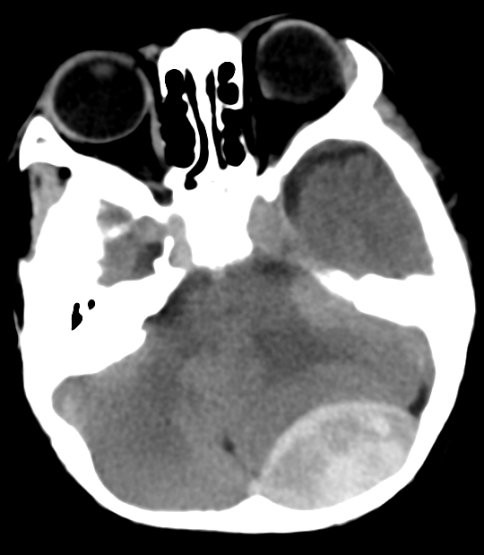

时间就是生命!到院后,急救团队立即对明明进行吸氧等紧急处理,待生命体征稳定后,送行头部CT检查,结果显示左枕部急性硬膜外血肿,血肿已超过10ml,已压迫到了小脑及脑干,导致脑组织移位,极易形成脑疝。患儿病情危重,随时可能因为脑疝出现脑功能衰竭死亡。

最终,由神经外科韦庆利主任医师、王圣泳主治医师、黄静主治医师及麻醉科医生护士成立的手术救治团队,为患儿实施开颅血肿清除术。整个手术历时约2小时,手术过程顺利,术后复查颅内出血完全清除,并转入重症监护室继续治疗。术后第6天,明明被转入普通病房。